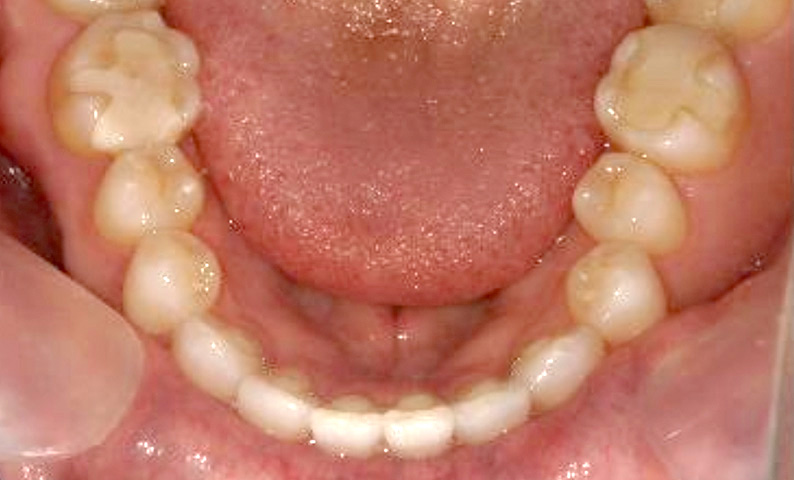

症例_003 下顎だけの部分矯正

治療期間:10ヶ月金額:24万円+税女性前歯のガタガタ下の前歯だけ上顎は補綴治療中

| Before | After |